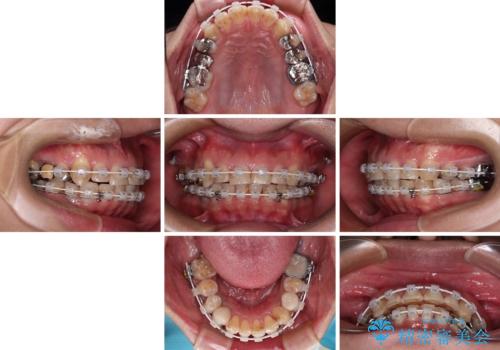

- 矯正装置

- 審美装置

- 治療期間

- 2年3ヶ月

- 治療回数

- 30回以上